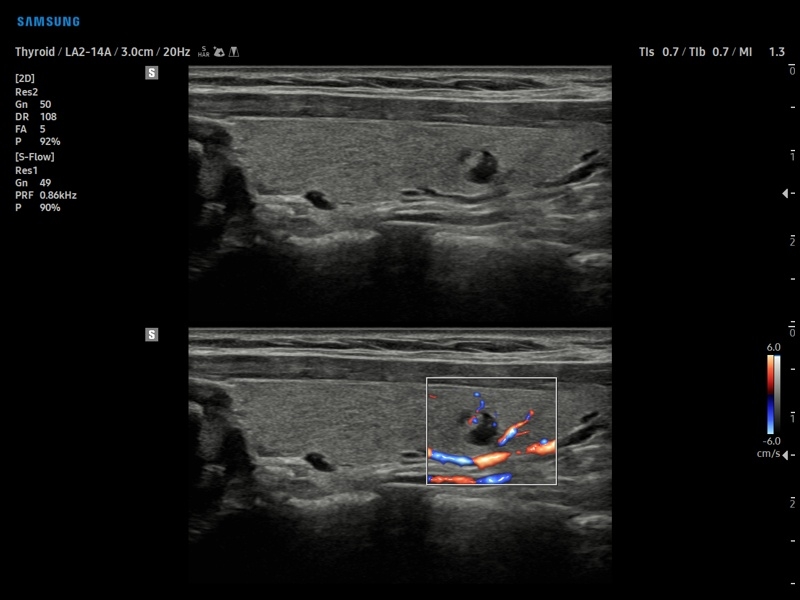

Ультразвуковой сканер V8-RUS является экспертным классом (премиальный уровень) и производится компанией Samsung Medison. Сканер V8 обеспечивает превосходное качество изображения благодаря использованию технологии Crystal Architecture™, которая включает в себя передовое аппаратное обеспечение, монокристальную технологию изготовления датчиков и сложную программную обработку ультразвуковых лучей.

• S-Detect для исследования молочной железы и щитовидной железы

• МодульS-Detect Thyroid- программа автоматического обнаружения образований и анализа щитовидной железы, измерение и классификация по системе системе TI-RADS.

• Модуль S-Detect Thyroid - программа автоматического обнаружения образований и анализа щитовидной железы, измерение и классификация по системе системе TI-RADS.